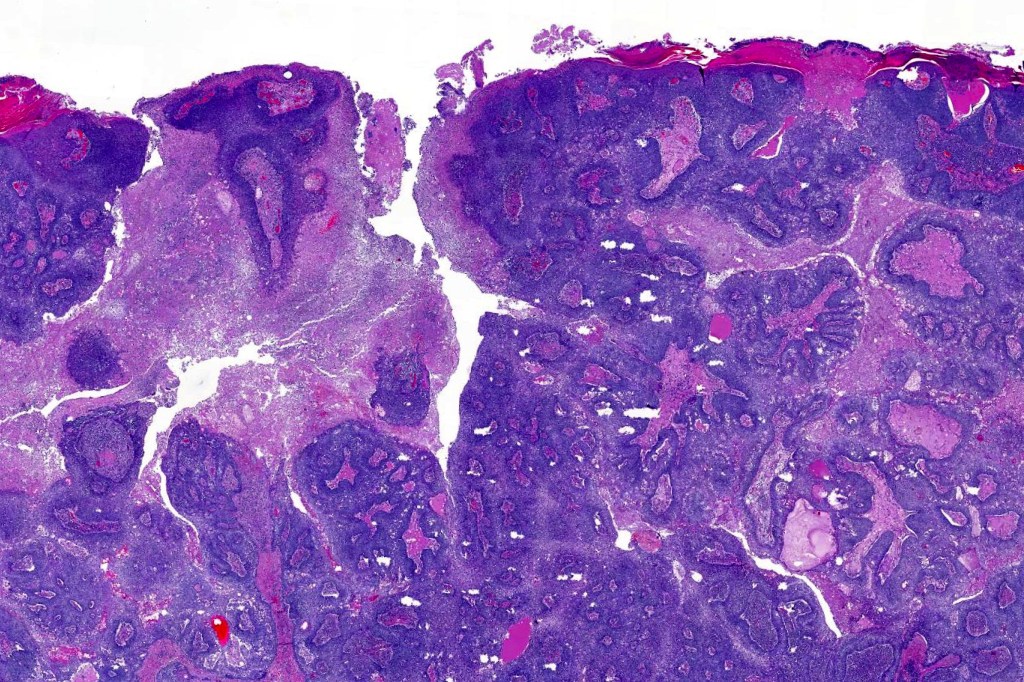

•Well differentiated lobular growth pattern though to a poorly differentiated tumor often showing a diffuse, infiltrating border which may extend into the subcutaneous fat

•Comedo type necrosis commonly present

•Tumors are composed of an admixture of darkly staining basaloid cells with hyperchromatic or vesicular nuclei and more obvious sebaceous cells with eosinophilic, bubbly, multivacuolated cytoplasm frequently indenting the nucleus (scalloped)

•Focal squamous differentiation with keratinization can be present resulting in confusion with squamous cell carcinoma